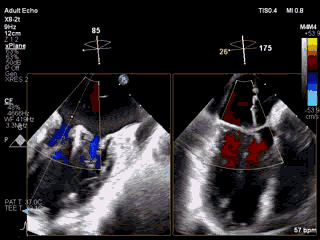

视频6 经食道三维超声心动图显示在植入第二枚MitraClip NTR夹合器后,二尖瓣呈双孔启闭,两枚夹合器位置、结构正常

视频7 经食道三维超声心动图(配备最新心腔镜功能)TrueVue彩色多普勒显示二尖瓣夹合术后二尖瓣反流降至少量

图1 两枚夹合器植入后,未致二尖瓣口狭窄,二尖瓣平均跨瓣压差为3mmHg

4月11日上午患者在全麻下接受MitraClip经皮二尖瓣夹合术。术中穿刺右股静脉,经食道超声心动图(TEE)再次评估瓣膜病变(视频1),并引导顺利穿刺房间隔(视频2)。随后送入二尖瓣夹合系统,在TEE引导下于二尖瓣P2区植入MitraClip XTR夹合器一枚(视频3),二尖瓣关闭不全减轻,但夹合器内侧仍存在反流(视频4)。团队决定为患者植入第二枚夹合器(MitraClip NTR),手术过程顺利(视频5)。TEE三维显示在植入第二枚NTR夹合器后,二尖瓣呈双孔启闭,两枚夹合器位置、结构正常(视频6)。配备心腔镜功能的TEE三维TrueVue彩色多普勒显示二尖瓣反流将至少量(视频7),且未致二尖瓣口狭窄(图1),夹合效果满意。手术通过视频连线得到香港亚洲心脏病中心主任林逸贤教授的技术支持。